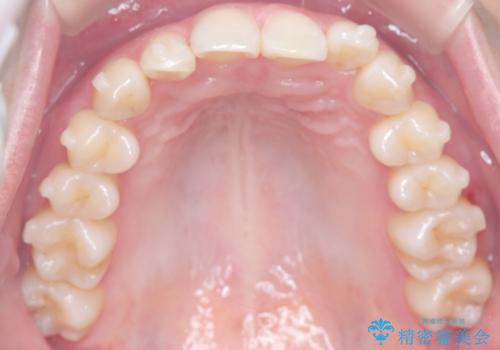

インビザライン矯正|下顎前歯1本抜歯でスムーズに歯列改善(1年で完了)

- 患者様は、下顎前歯のガタつきを改善したいとのことで来院されました。診察の結果、スペース不足により前歯が重なっている状態でした。抜歯をせずに並べると前歯が前方に突出してしまうため、下顎の前歯を1本抜歯し、インビザラインで矯正する治療計画を立てました。できる限り追加のアライナーを使用せずに治療を完了できるよう、初回の治療計画を慎重に設計しました。

下顎前歯を1本抜歯し、歯列のスペースを確保。その後、インビザラインを用いて計画通りに歯を移動させ、噛み合わせも整えました。患者様の協力もあり、ゴムかけなどを適切に行い、予定通り1年で治療を完了。追加アライナーを使用することなく、計画通りに治療を終えることができました。患者様からは「思ったより早く終わり、仕上がりにも満足している」と喜びの声をいただきました。